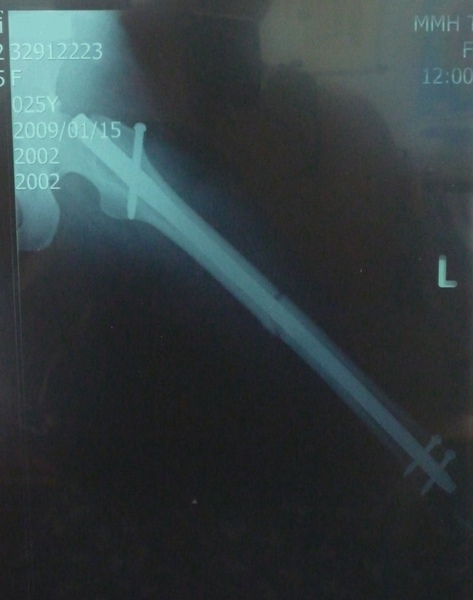

看到鋼釘拿出來的粗細與重量,我真嚇到了

著實有34cm(我大腿的長度呢!),幫它秤了一下體重,有兩百克呢!

整支鋼釘都還閃亮亮的全新

我仿照X光片打鋼釘的方式,重新擺了一次 (這是上半部)

鋼釘的兩端都好尖銳,難怪放在身體裡會有不適

這是靠近膝蓋處,兩根螺絲真是折騰我了